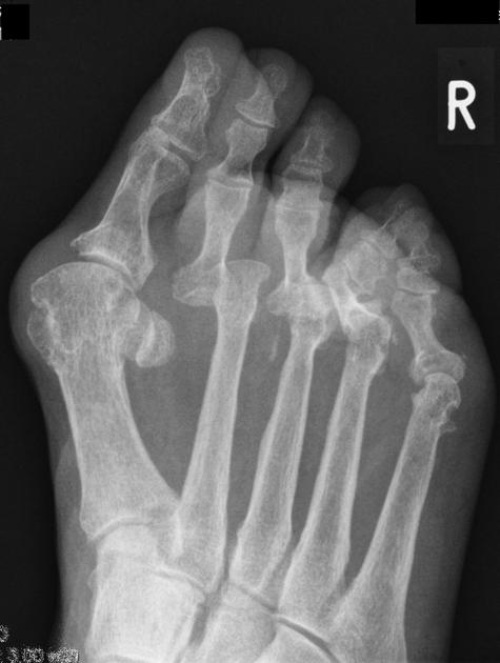

Hình ảnh X-quang ở chân

Hình ảnh X-quang cho thấy tình trạng biến dạng vẹo ngón chân và những bất thường khác, đi kèm với giảm mật độ xương ở bệnh nhân viêm khớp dạng thấp. Ảnh: Radiopaedia

Hình ảnh Xquang ở bàn chân

Ảnh X-quang bàn chân ở một bệnh nhân nữ 55 tuổi bị viêm khớp dạng thấp với tình trạng mòn khớp, biến dạng trật khớp ở khớp đốt bàn – ngón chân. Ảnh: Radiopaedia